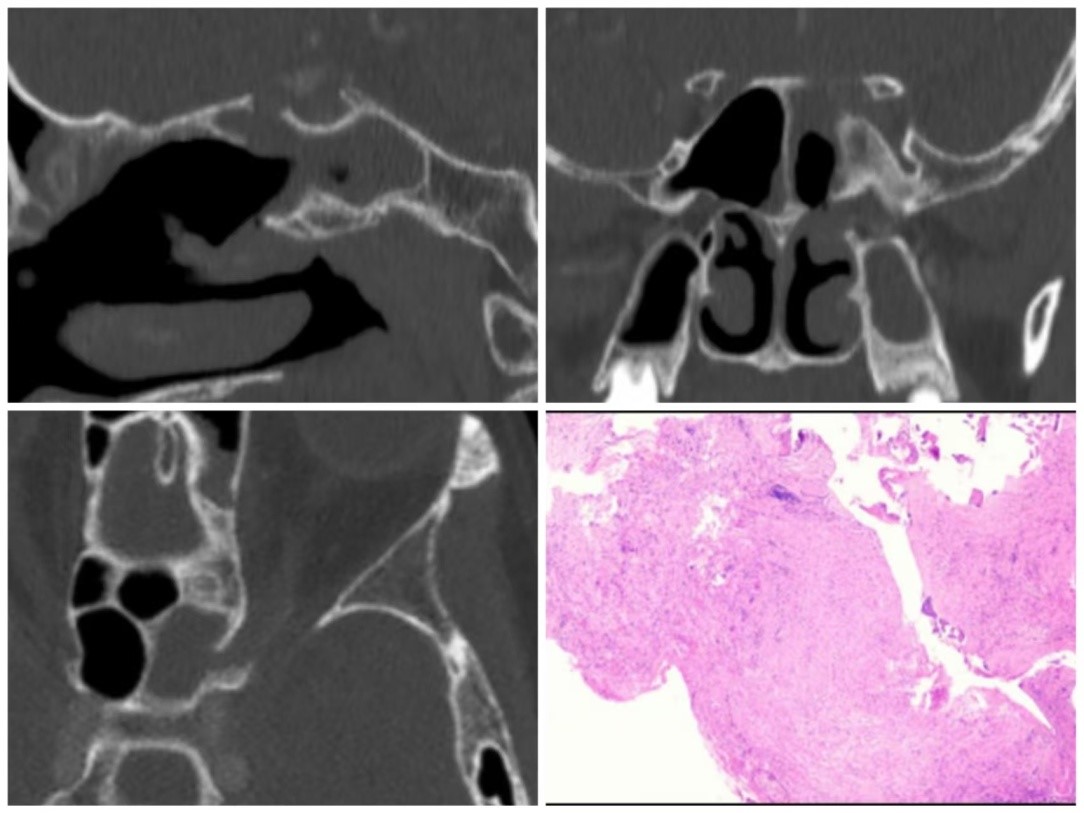

近日,我院凭借精湛的内镜微创技术,救治了一名66岁侵袭性真菌性蝶窦炎、视神经炎患者,助其恢复视力。患者先前因头痛和视力减退在外院就诊并接受手术治疗,但术后未能明确诊断导致治疗效果不佳。转入我院后,患者左眼已完全失去视力,无光感,头痛剧烈,经诊断发现霉菌组织侵犯视神经周围及鼻颅底区域。若不及时干预,将面临永久性失明、病变波及颅内甚至危及生命的风险。

我院鼻颅底专业医疗团队在王德辉教授的带领下,迅速开展多学科会诊,综合多方意见,精准研判、周密制定手术方案,采用内镜微创技术,精细切除视神经周围及鼻颅底受霉菌侵犯的病变组织。与此同时,视神经减压术同步实施,精准清除病灶、解除视神经压迫,最大程度保护正常组织与神经功能,并给予患者抗真菌治疗。术后,患者头痛已基本缓解,病理报告证实急性侵袭性霉菌病,视神经受真菌侵蚀。